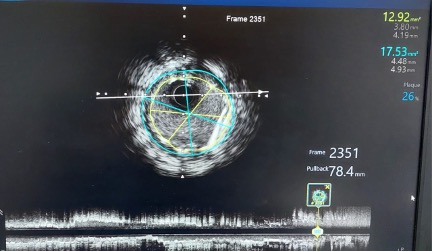

A second DES (Resolute Onyx, Medtronic) was then deployed from the proximal LAD into the LMS, effectively jailing the wire fragments. IVUS assessment was performed from the ostial LAD (Figure 4A-C, Video 5).

Final angiography confirmed TIMI-3 flow with no dissection, perforation, or distal embolization; the wire in the side branch remained in place at the end of the procedure (Figures 2 [white arrow], 4A-C, 5, Video 6).